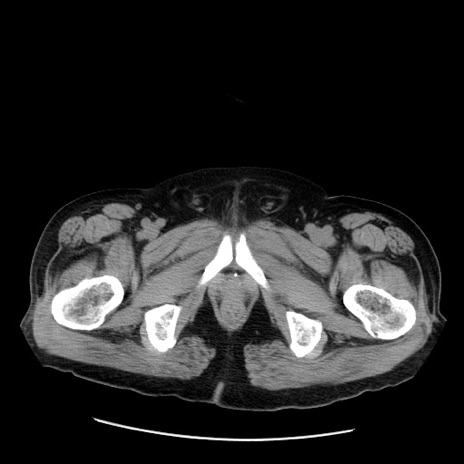

症例20(横断像)

【症例】 60歳代男性

【主訴】 腹部膨満、嘔吐

【現病歴】5日前頃より倦怠感を認め食事量減少し4日前の朝嘔吐、食事摂取困難となった。 3日前近医受診し点滴施行され整腸剤などを処方された。 当日他院を受診し、腹部膨満著明、炎症反応の上昇(CRP10.8、WBC11200)あり、紹介受診となる。

【身体所見】 意識JCS1 受け答えがはっきりしないBP 111/57mHg、 P 67bpm、、BT35.2°C、SpO2 97%(RA)、 腹部:膨隆、打診で鼓音あり、全体的に圧痛有り、腸蠕動音(-)、反跳痛ははっきりせず。

【データ】WBC 11400、CRP 14.20